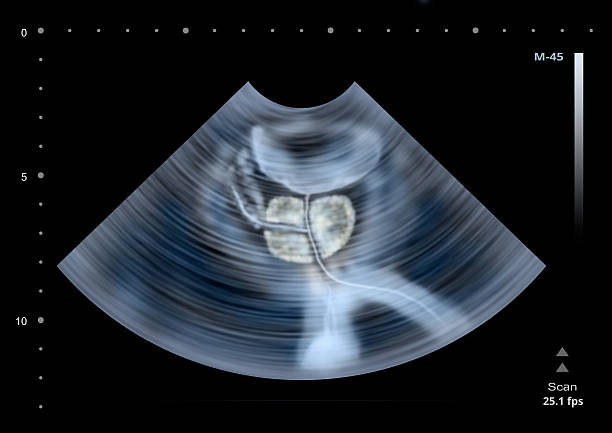

초음파 치료

이 방법은 고주파 음파를 이용하여 전립선 조직을 소멸시키는 것입니다. 이 방법은 고효율이며 합병증이 적은 것으로 알려져 있습니다. 초음파 치료는 일반적으로 중등도의 전립선비대증 증상을 가진 환자에게 시행되며, 침습적인 방법에 비해 회복 기간이 짧은 장점이 있습니다.